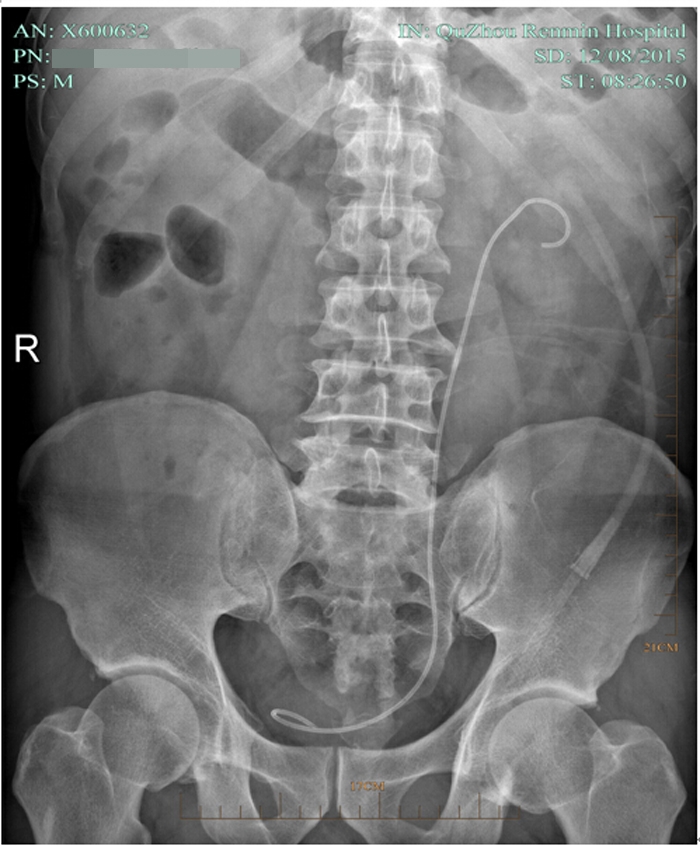

??? 術(shù)后第七天,復(fù)查泌尿系平片無結(jié)石殘留,拔了腎造瘺管出院。因為腎結(jié)石手術(shù)都需要放置輸尿管支架管,出院時護(hù)士叮囑出院后要多喝水,避免活動過多引起血尿,1個月后來拔支架管。

術(shù)后復(fù)查平片

術(shù)后復(fù)查泌尿系平片